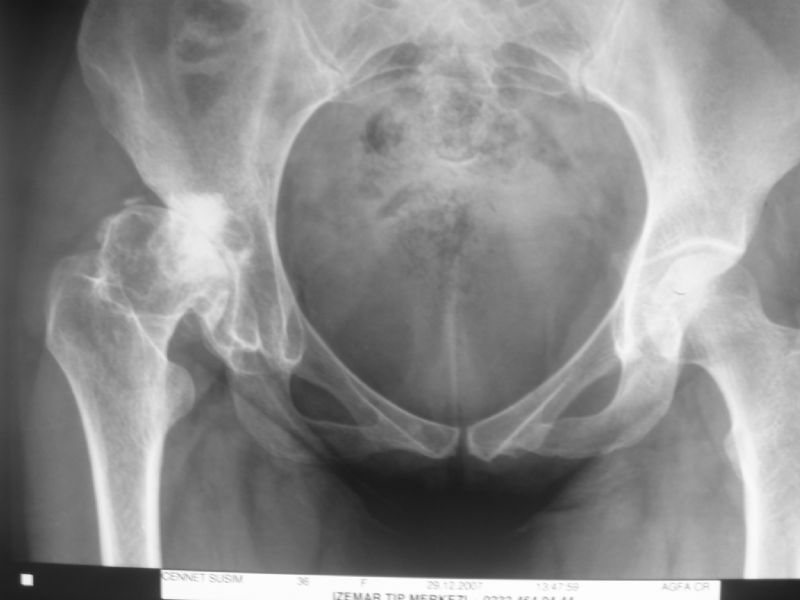

Total Kalça Protezi Örnek Olgular